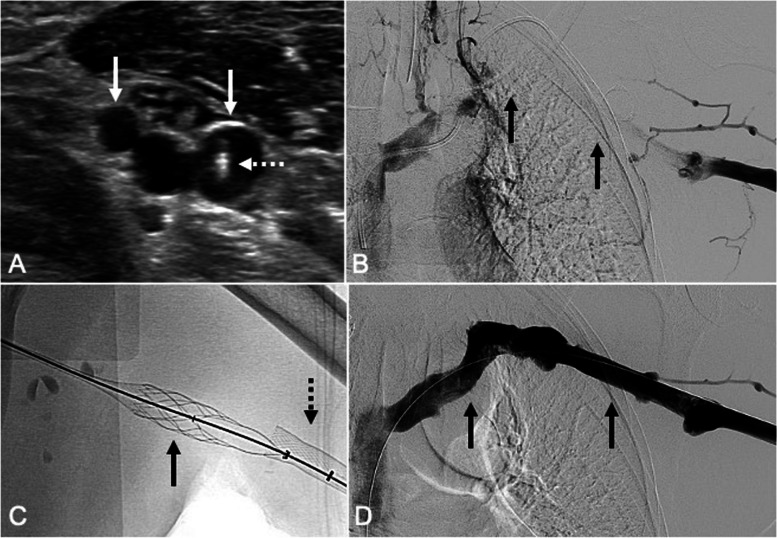

Results: Fourteen patients (8 males, 6 females; mean age 51.7 ± 13.6 years) comprising 16 upper extremity venous access sites were included in this study. Access sites included: right brachial (n = 7), left brachial (n = 5), and bilateral brachial (n = 2) veins. The mean access site diameter was 4.3-mm ± 0.67-mm. Technical success was achieved via all access sites. Six (42.9%) patients underwent stent reconstruction following thrombectomy through the same accesses. After the procedure, all purse-string sutures were removed within 24 h. Three (21.4%) patients experienced small access site hematomas that did not require transfusion, intervention, or prolonged hospitalization. Initial follow-up venous duplex ultrasounds were performed at 29.3 ± 21.7 days following intervention. The mean follow-up interval to the second and third venous duplex ultrasounds were 124.3 ± 64-days and 225.1 ± 80.1 days, respectively. One (7.1%) patient developed right arm swelling six days after the procedure and was found to have thrombosis of the previously accessed right brachial vein. No other clinically or sonographically significant access site adverse events were observed.